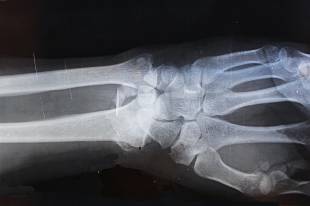

가벼운 충격에도 관절 주변에서 잦은 통증이 발생하는 모습이 대표적입니다. 계단을 내려갈 때 무릎이 순간적으로 끊기는 듯한 느낌이 들거나, 손잡이를 잡기 위해 손목을 비트는 사소한 동작에서도 통증이 쉽게 나타납니다. 이는 단순 근육 피로가 아니라 골소주의 강도가 저하될 때 발생하는 미세 응력 집중 현상과 관련이 있습니다.

익숙한 움직임에서도 제동이 걸릴 때가 있습니다. 바닥에 떨어진 물건을 줍기 위해 허리를 숙였다가 갑작스러운 불편감을 느끼거나, 고관절이 예상보다 빠르게 뻣뻣해지는 느낌을 받을 수 있습니다. 이는 관절 주변을 보호하는 골피질이 약해지면서 작은 회전력에도 주변 조직이 과도하게 긴장하는 현상으로 이해할 수 있습니다.